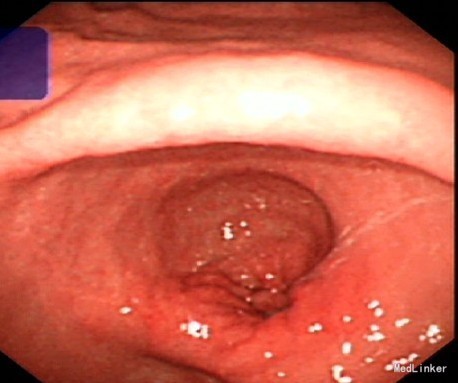

查体:体温:36.5℃ 呼吸:20次/分 脉搏:78次/分 血压:125/75mmHg, 腹部膨隆,以上腹明显,无胃型、肠型、蠕动波,腹式呼吸存在,腹壁静脉无曲张。腹肌柔软,无压痛、反跳痛,无液波震颤,未触及腹部包块,肝脏肋下未触及,脾脏肋下未触及,肾脏未触及,输尿管压痛点无压痛,Murphy 征阴性,腹部叩诊鼓音,肝浊音界存在,移动性浊音阴性,肾区无叩击痛,无振水声,肠鸣音正常,未闻及腹部血管杂音。 入院查腹部CT示:胃明显扩张及大量潴留液、胃窦幽门管管壁增厚、粘膜肿胀,考虑胃幽门梗阻。建议胃镜检查。 胃镜示(见图2):胃溃疡并胃窦狭窄、并不全梗阻,予多点活检未见癌 血生化示血常规正常,肝功能、肾功能正常,CEA、AFP、CA19-9、CA-125、CA72-4、CA15-3均正常 粪便转铁蛋白测定:转铁蛋白 阳性(+),OB(+)